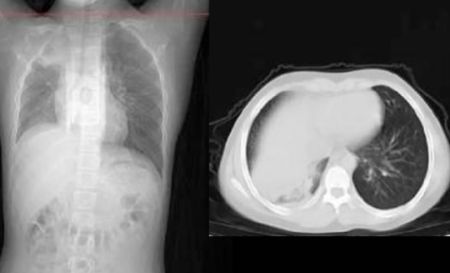

与此同时,马萨诸塞州西部还出现了大量“行走性肺炎”病例。这个“行走性肺炎”是由细菌和病毒感染的混合物引起的,是一种比较温和的肺部疾病,患者会出现发烧和咳嗽的症状,但是没有痰。儿科医院的凯利医生接受采访时表示,现在正是呼吸道病毒 RSV 的流行季节,很多孩子患有上病毒性呼吸道感染、咳嗽、流鼻涕,还有一些发烧,对肺部也有影响。

现阶段,80%患有“行走性肺炎”的儿童是由于首次感染RSV引起的,20%病例是由细菌引起的,可用抗生素治疗。对于此波疫情,美国卫生当局也提出了几种可能性,其中之一就是大流行期间的封锁、戴口罩和关校一定程度上削弱了儿童的免疫力,使他们在疫后更容易患上季节性疾病。

马萨诸塞州的医生表示,这次疫情的主要问题是呼吸道合胞病毒RSV,这是一种呼吸道病毒,每年导致10000多名美国人死亡,其中大多数是幼儿和老人。“现在就是RSV的高发季节,我们看到了很多孩子患有上层病毒性呼吸道感染、咳嗽、流鼻涕、发烧,而RSV会导致下层病毒性呼吸道感染,传播到肺部。欧洲的荷兰和丹麦也正在经历类似的感染潮,“神秘”肺炎病例达到峰值。秋冬本来就是各种呼吸道疾病的流行季节,年底了,各种聚会越来越多,希望大家都做好预防措施。(来源:加西周末)